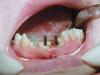

Doc Опубликовано 23 октября, 2008 Поделиться Опубликовано 23 октября, 2008 А почему такая уверенность, что вывалятся? Думаю, что доктору не нравится тот факт, что у всех трех культей есть явное погружение истонченного края под десну и этот факт не был должным образом учтен. Потому возможно микроподтекание, сложная фиксация и невозможность создания адекватного ферула и уступа. Но что касается трех лет, то я бы не был столь категоричен. Срок службы работы зависит от такого большого количества факторов, что по одной фотографии так сразу предсказать его нереально. Ссылка на комментарий

y_veselchak Опубликовано 24 октября, 2008 Поделиться Опубликовано 24 октября, 2008 Думаю, что доктору не нравится тот факт, что у всех трех культей есть явное погружение истонченного края под десну и этот факт не был должным образом учтен. Потому возможно микроподтекание, сложная фиксация и невозможность создания адекватного ферула и уступа. Но что касается трех лет, то я бы не был столь категоричен. Срок службы работы зависит от такого большого количества факторов, что по одной фотографии так сразу предсказать его нереально.Я с большим удовольствием в свое время посетил Вашу лекцию по ВКВ, почерпнул массу интересого и стараюсь. Принимая во внимение исходную картину, вот что получилось во рту - критикуйте Ссылка на комментарий